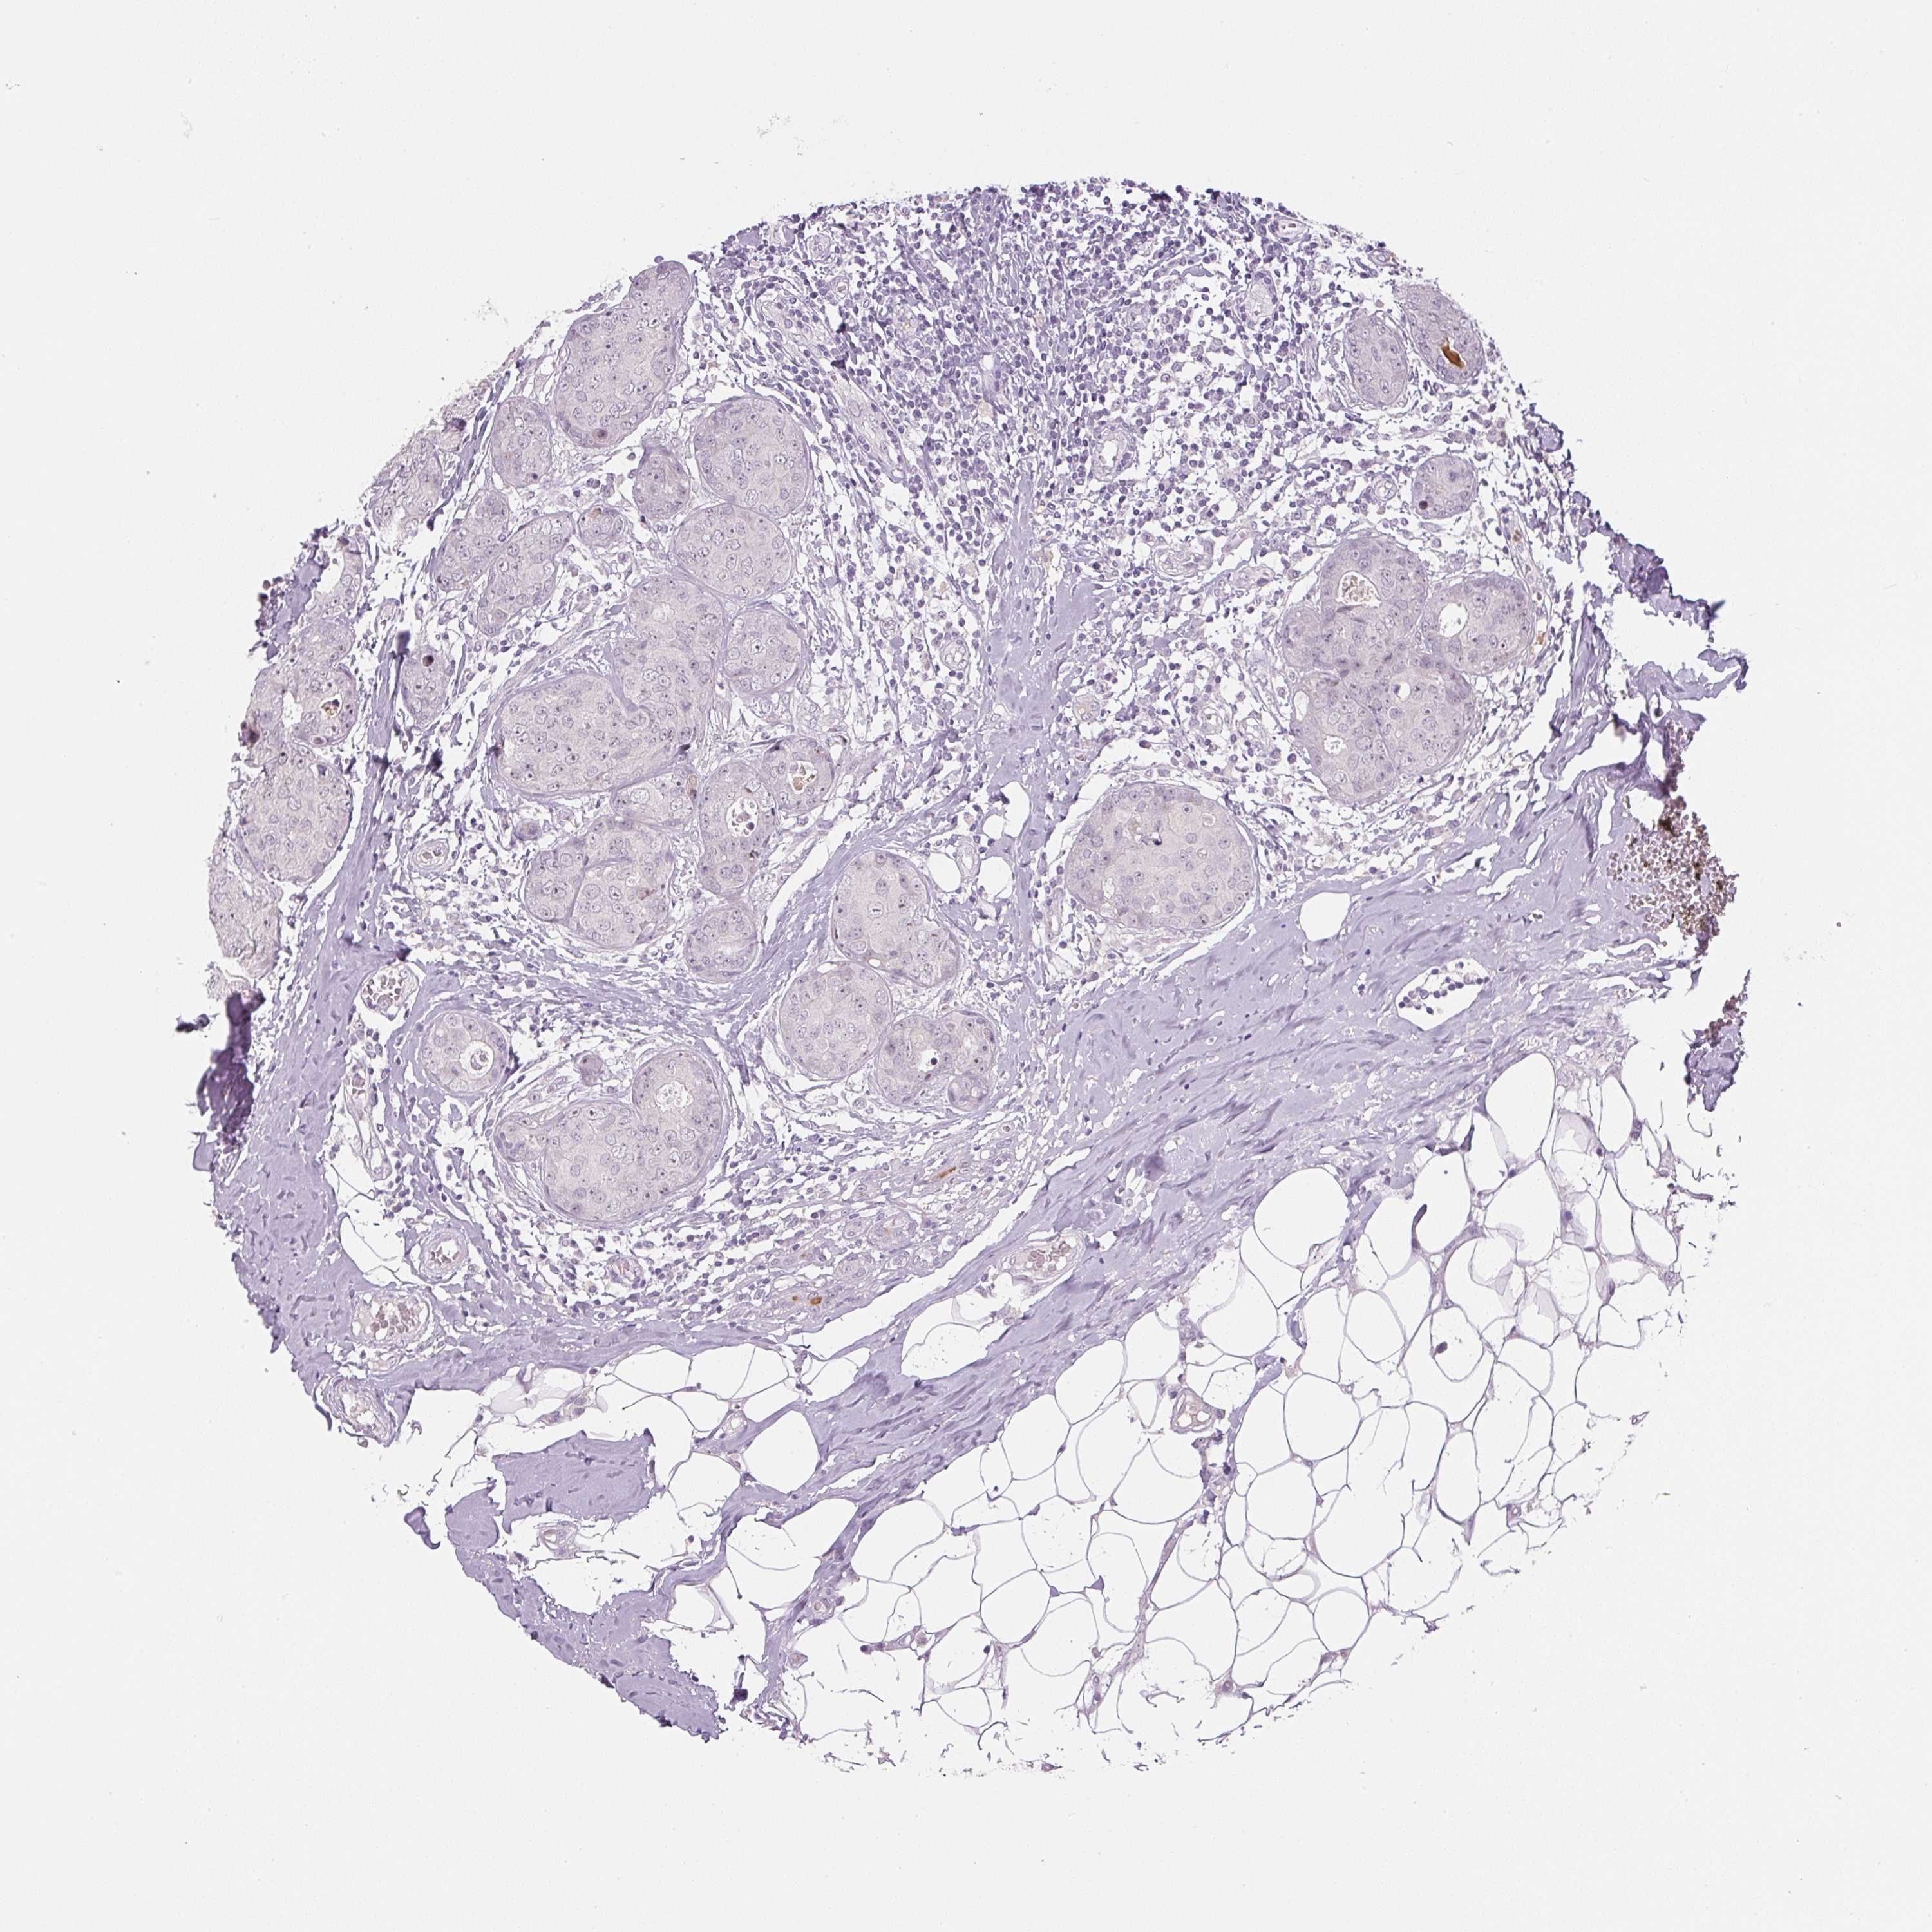

Breast cancer

Human cancer